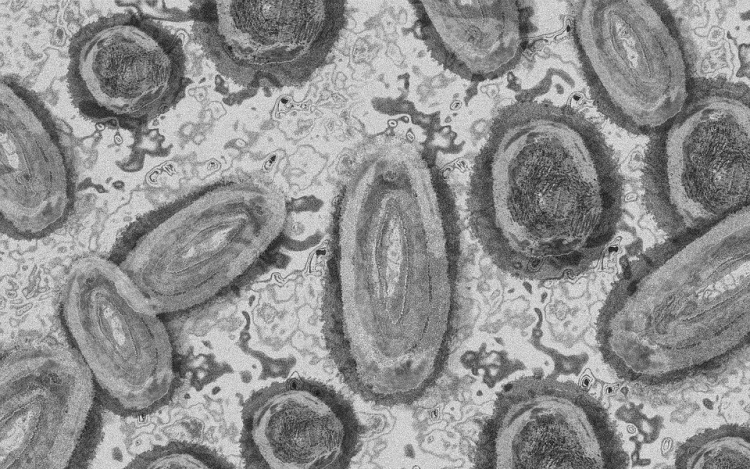

Megfertőződött a majomhimlővel egy gyerek Németországban

Megfertőződött majomhimlővel egy négyéves kislány Németországban - jelentették kedden német hírportálok az országos közegészségügyi intézet (RKI) adatai alapján.

Németországban első alkalommal mutatták ki a kórokozót gyermek szervezetében.

A kislány két fertőzött felnőttel él együtt a Baden-Württemberg tartományi Pforzheimben. A tartományi egészségügyi minisztérium tájékoztatása szerint elővigyázatosságból vizsgálták meg, miután kimutatták az első fertőzést a háztartásban. Eddig nem jelentkeztek nála a betegség tünetei.

Az RKI-nál május elején regisztrálták az első németországi majomhimlős eseteket. Keddig 2982 igazolt fertőződést jegyeztek fel. A betegség mind a 16 tartományban megjelent.

Az intézet ismeretei szerint a vírus elsősorban szexuális úton terjed Németországban, főleg férfiak körében. A fertőzöttek szinte mind felnőtt férfiak, csupán hét nő és két kiskorú - egy 15 és egy 17 éves kamasz - van közöttük.

Az esetek többségében a fertőzés enyhe lefolyású betegséggel jár. Halálos áldozatot Németországban még nem regisztráltak.

Az Afrika egyes részein évtizedek óta ismert és ritkán előforduló majomhimlő május óta Európában, Észak-Afrikában és más térségekben is terjed. Az Egészségügyi Világszervezet (WHO) júliusban globális egészségügyi vészhelyzetnek nyilvánította a járványt.